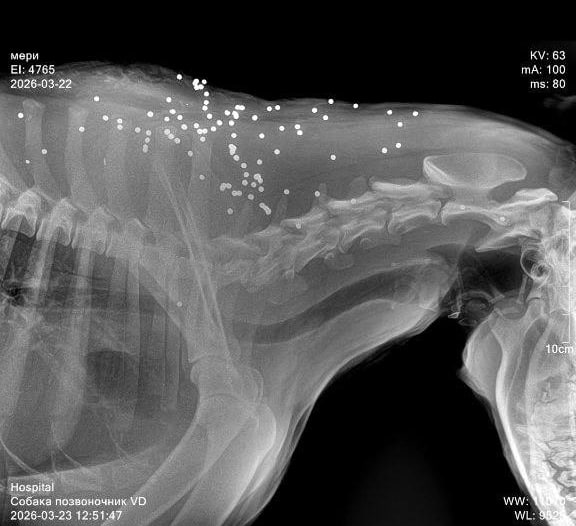

В результате нападения одна собака погибла, пострадали еще как минимум три. Двое пострадавших псов убежали, а третьего экстренно доставили в ветеринарную клинику, сообщают местные. Полиция проводит проверку.